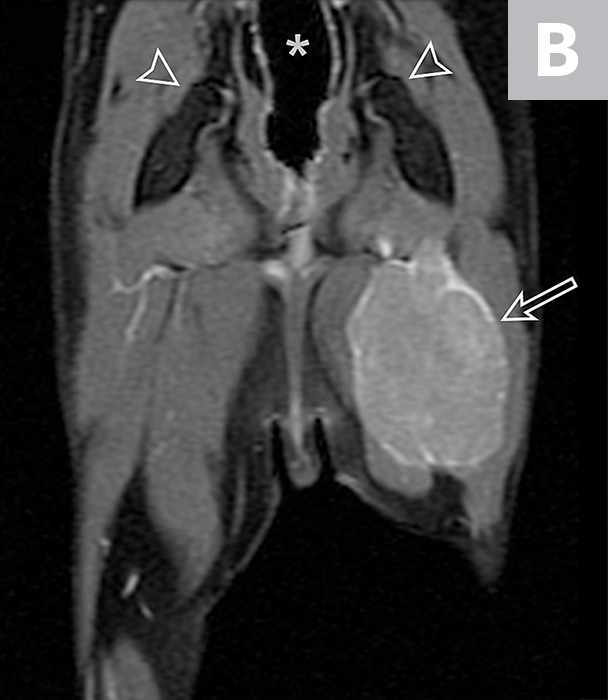

From radiologykey.com

Thymic Epithelial Neoplasms Radiology Key Thymic Neoplasm Feline Thymic tumors are abnormal growths of tissues of the thymus gland, and are rare in cats. Its cause is unknown, and diagnosis. A thymoma is a tumor originating from the epithelium of the thymus (the layer of tissue covering the thymus). In this report, we present the full diagnostic characteristics of a young cat with a cranial mediastinal mass diagnosed. Thymic Neoplasm Feline.

Thymic Epithelial Neoplasms Radiology Key Thymic Neoplasm Feline In this report, we present the full diagnostic characteristics of a young cat with a cranial mediastinal mass diagnosed as a cystic type. Its cause is unknown, and diagnosis. Thymic tumors are abnormal growths of tissues of the thymus gland, and are rare in cats. Thymoma is a rare neoplasm seen in aged cats that derives from thymic epithelial cells. Thymic Neoplasm Feline.